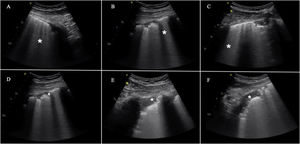

The most frequent findings in patients with acute respiratory failure associated with COVID-19.

This includes the presence of B lines in all their possible forms, even to the point of forming a “white lung” image. They may arise from the pleural line or from small peripheral consolidations. A) Separated B lines. B) Coalescent B lines. C) “White lung”. D) Irregular and fragmented pleural line. E) and F) Subpleural consolidations.

Although none of these signs are specific of COVID-19 pneumonia, the distribution of such alterations in a concrete epidemiological scenario implies great specificity. Bilateral involvement in the form of patchy groups of B lines coexisting with other “free” lung zones is characteristic.10,12 The lesions exhibit a peripheral distribution and predominate in the posteroinferior fields, extending to lateral and anterior regions as the disease progresses. In contrast, the appearance of significant pleural effusion or large lobar consolidations makes it necessary to take other alternative diagnoses or complications into account.12